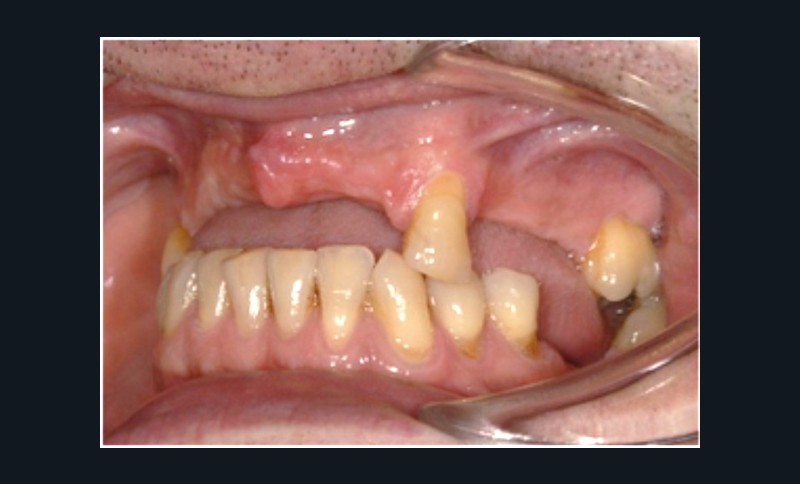

Cette partie de la présentation ne se contentait pas de rapporter les principes précédemment décrits à des régions limitées des maxillaires mais étendait la discussion à la difficulté majeure rencontrée en implantologie : rattraper des erreurs de positionnement implantaire ayant entraîné des compromis prothétiques inesthétiques. La solution thérapeutique mise en œuvre par Benoît Philippe consiste à appliquer la procédure d’ostéotomie segmentaire à l’entité constituée par l’os alvéolaire péri-implantaire et les implants. Les couronnes implantaires sont déposées. Le tracé d’ostéotomie encadre le segment à repositionner mais n’implique pas la corticale palatine qui sera fracturée pour éviter toute lésion du périoste (nourricier du segment alvéolo-implantaire). Un dispositif prothétique préparé en amont guide la translation du fragment qui est fixé au moyen de plaque d’ostéosynthèse dans la situation idéale. Le capital squelettique est reconstruit et l’espace prothétique disponible est normalisé.

Au cours de la conférence, Benoît Philippe a énoncé ses convictions concernant les conditions de succès du traitement implanto- prothétique : le respect d’une biomécanique implantaire équilibrée, le recours à des implants plus fins et moins nombreux que ne l’imposaient les préconisations d’autrefois, l’observation du biotype parodontal plus ou moins favorable aux reconstructions des atrophies étendues, la nécessité de restaurer au préalable puis de maintenir un environnement parodontal satisfaisant (en particulier la gencive attachée péri-implantaire).